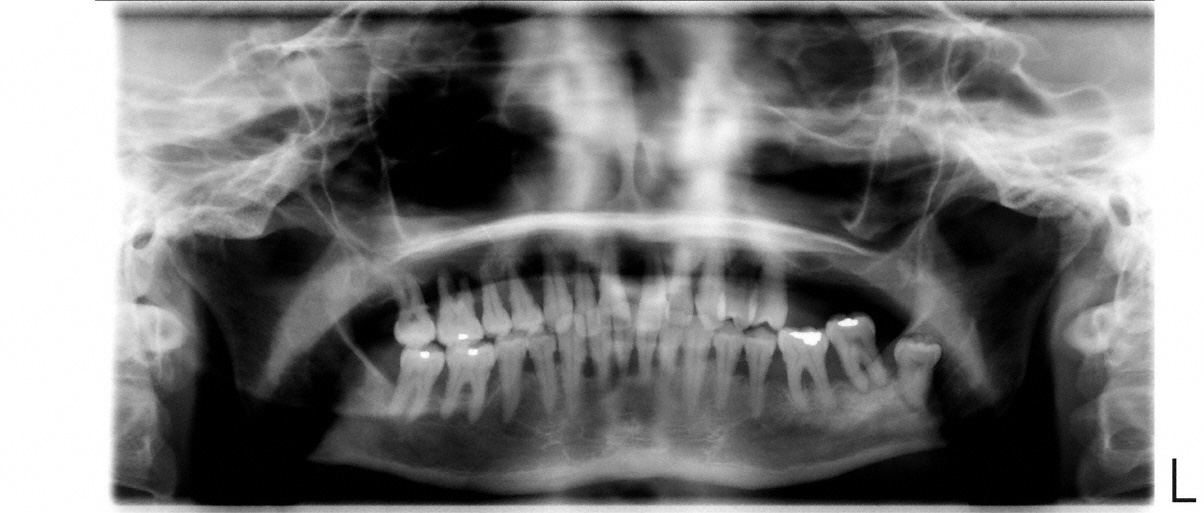

Eine initiale Diagnostik kann eine Fotodokumentation, die Bestimmung diverser Indizes (z. B. Plaqueindex, API) und Röntgenaufnahmen beinhalten. Bei den Röntgenaufnahmen wird in der Regel eine Panoramaaufnahme angefertigt. Von nicht vital reagierenden und wurzelgefüllten sowie nicht auf der Aufnahme ausreichend erkennbaren Zähnen werden Zahnfilme erstellt. Unter Umständen kann eine Aufnahme aller Zähne mittels Zahnfilmen anstelle einer Panoramaaufnahme erfolgen. Die Röntgendiagnostik gibt Auskunft über Zustand, Form und Beschaffenheit von Zahnhartsubstanz, Alveolenknochen (Knochen um den Zahn) und Restaurationen.